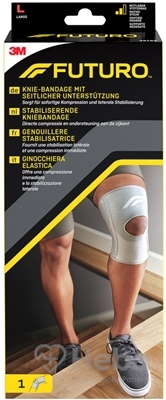

Ortéza slúži na akútne, subakútne a chronické bolestivé syndrómy relatívne nízkej intenzity rôznej etiológie, funkčné ošetrenie poranení kolenného kĺbu vyžadujúce obmedzenie rozsahu pohybu, poranenia a dysfunkcie bez nutnosti znehybnenia kĺbu, podpora väzivového kĺbu. aparát kolenného kĺbu.

Výrobok je vyrobený z polyamidového úpletu laminovaného neoprénom. Polycentrické vzpery ortézy umožňujú dvojité obmedzenie uhla flexie a extenzie. Systém upevňovacích popruhov ortézy umožňuje nastaviť tlak.

Ortéza má otvor na jabĺčko, ako aj odkrytú podkolennú jamku, ktorá umožňuje voľnú flexiu kĺbu.